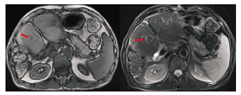

化疗后评估:腹部增强CT(2015年12月)提示:残肝多发占位结节,部分病灶较前增大(最大直径3.8 cm),未见新发病灶,见图4。肿瘤标记物:CEA为42.55 μg/L,血清CA19-9<0.60 U/ml,CA72-4为1.64 U/ml。整体疗效评估:病情进展(PD)。

患者完成5周期伊立替康+替吉奥方案化疗,综合评价为:PD。患者目前已是二线治疗方案,无使用靶向药物的条件,原发灶局部分期较晚,浸润广泛,手术可能无法达到R0切除,肝脏病灶为可切除病灶。可行腹腔镜探查术,了解病灶可切除性。若无法达到R0切除,可考虑原发灶及转移灶放疗。